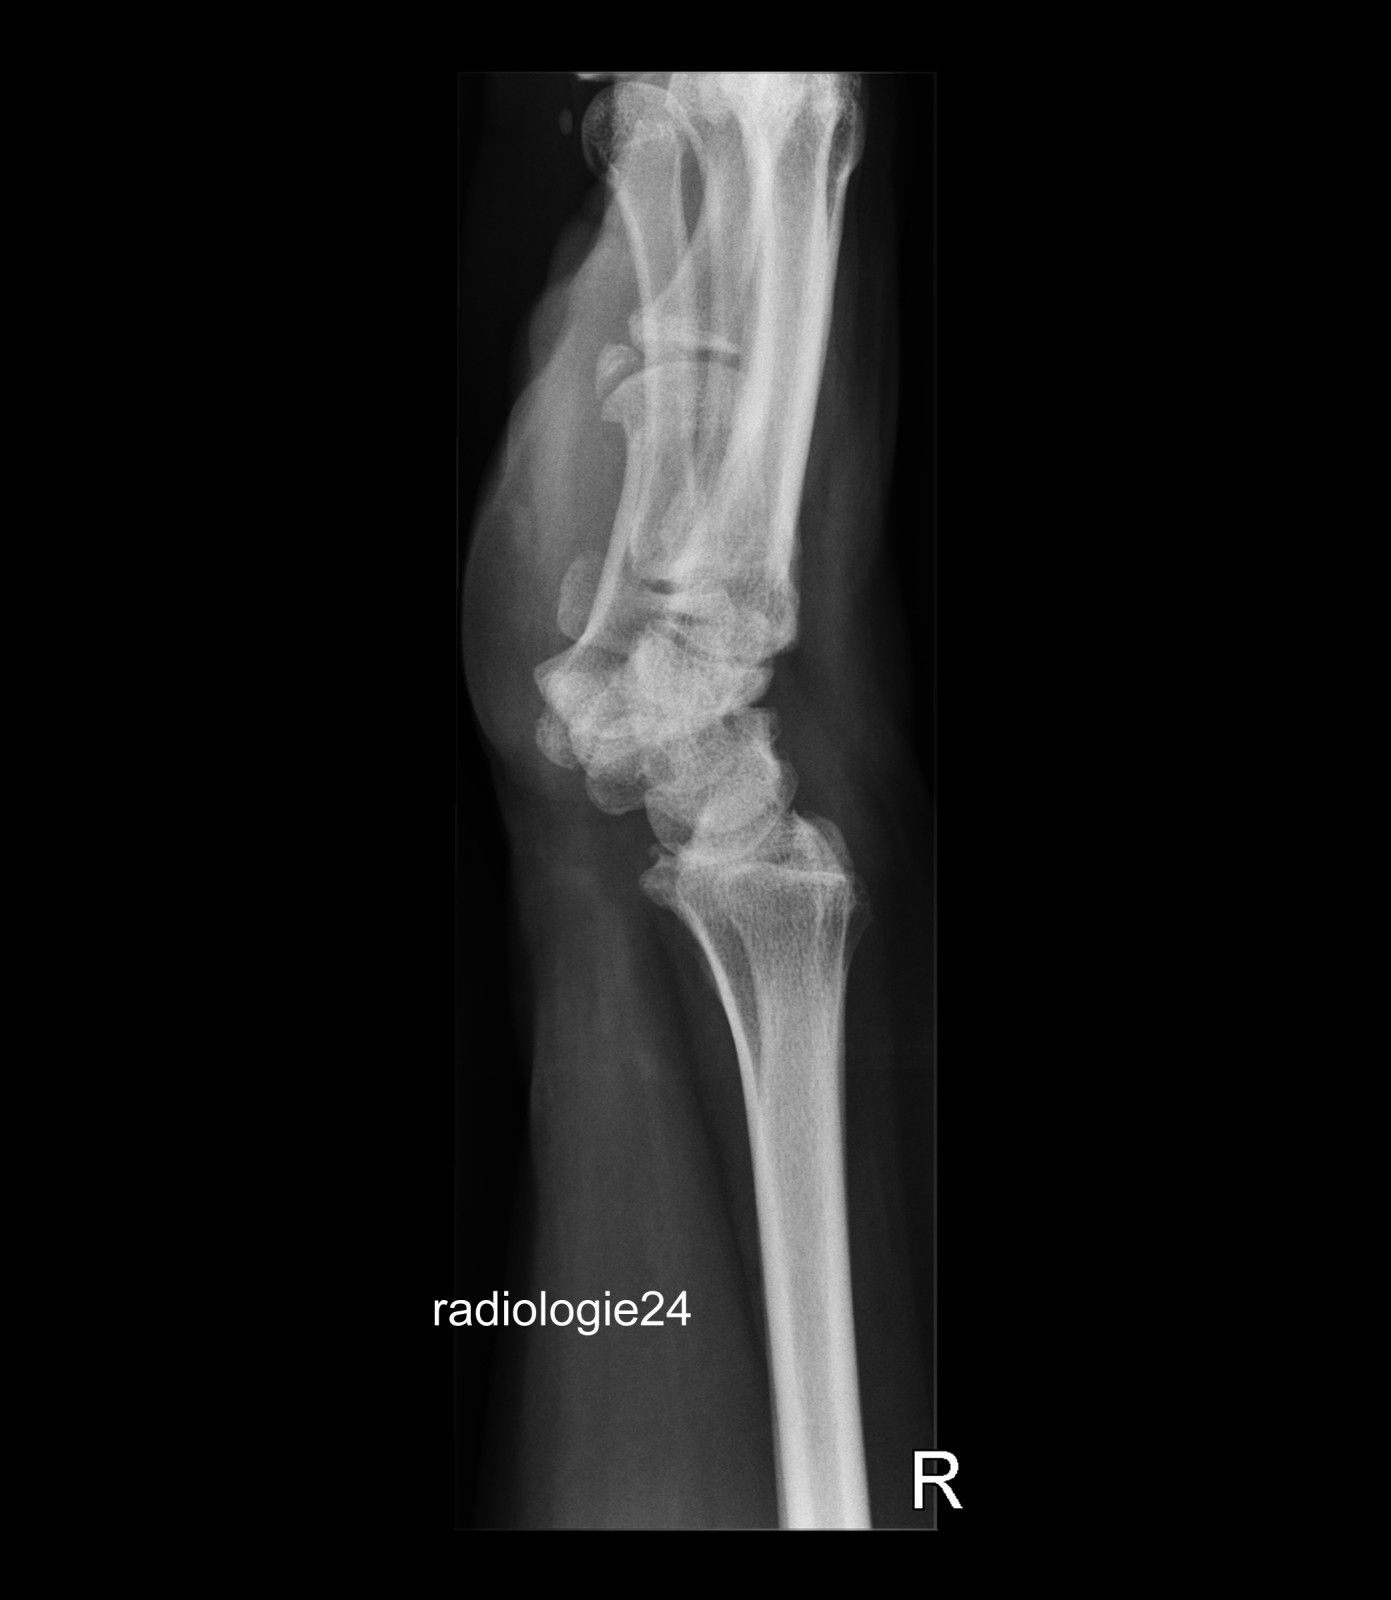

Röntgenfall des Monats Mai 2018 mit Auflösung

71 jähriger Patient Sturz auf die ausgestreckte Hand. Schmerzen. Ihre Diagnose? Weitere Abklärung?

Bild vergrössern

Link zur Auflösung mit ausführlichem Befund:

https://www.radiologie24.ch/radiologie-mediathek/roentgenfall_des_monats